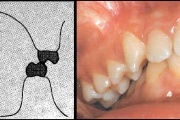

Lutipudelikaariese kahjustused

Lutipudelikaaries